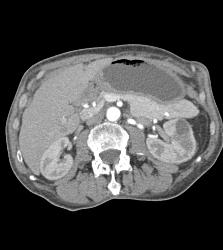

Antral Carcinoma With Celiac Nodes